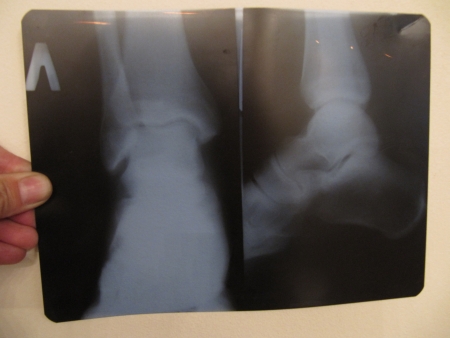

Na de noodzakelijke administratie worden er foto’s gemaakt. Zoals te verwachten is alles volgens de laatste technologische stand. Zie het mooie loden schort.

Vervolgens mocht ik met de ontwikkelde foto’s terug naar de dokter, die bepaalde dat mijn enkel gegipst moest worden.

Omdat de dames zelf niet goed konden zien of het gebroken is of niet, werden we doorverwezen naar het centrale ziekenhuis in de stad. Het aangebrachte gips dient enkel ter ondersteuning.

De foto’s worden opnieuw bekeken, op basis hiervan kunnen ze niet bepalen of het niet gebroken is, of dat er alleen een scheur inzit. Ik krijg een open gipsspalk en een lading recepten/aanbevelingen om allerlei, in mijn ogen, troep te gaan slikken.